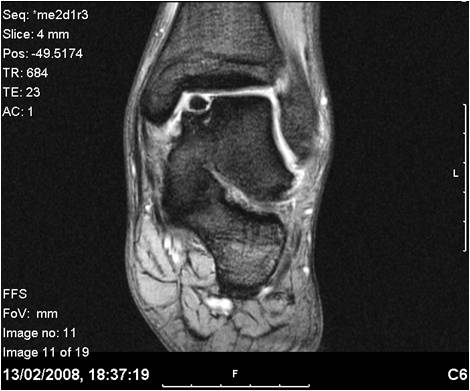

This can be explained by persistent soft tissue inflammation (impingement) or unrecognised injuries to tendons or the ankle joint surfaces, which may require further investigations with modern imaging techniques such as ultrasound and magnetic resonance scanning (MRI, Fig 2).